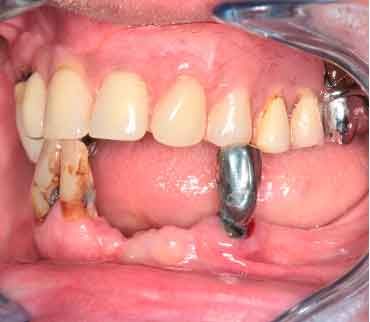

Patient de 66 ans. Souhaite retrouver un confort fonctionnel et améliorer l'esthétique.

- Manque de stabilité de ses prothèses amovibles

- Difficultés à manger

- Affaissement de la lèvre supérieure

Les structures parodontales des dents restantes ne sont plus suffisantes. Une édentation est envisagée. Le plan de traitement est orienté vers une prothèse complète maxillaire amovible et une prothèse complète mandibulaire supportée par des implants. Le défi est de passer de la situation initiale aux provisoires en utilisant les données du patient.

Photo - Situation intra-orale